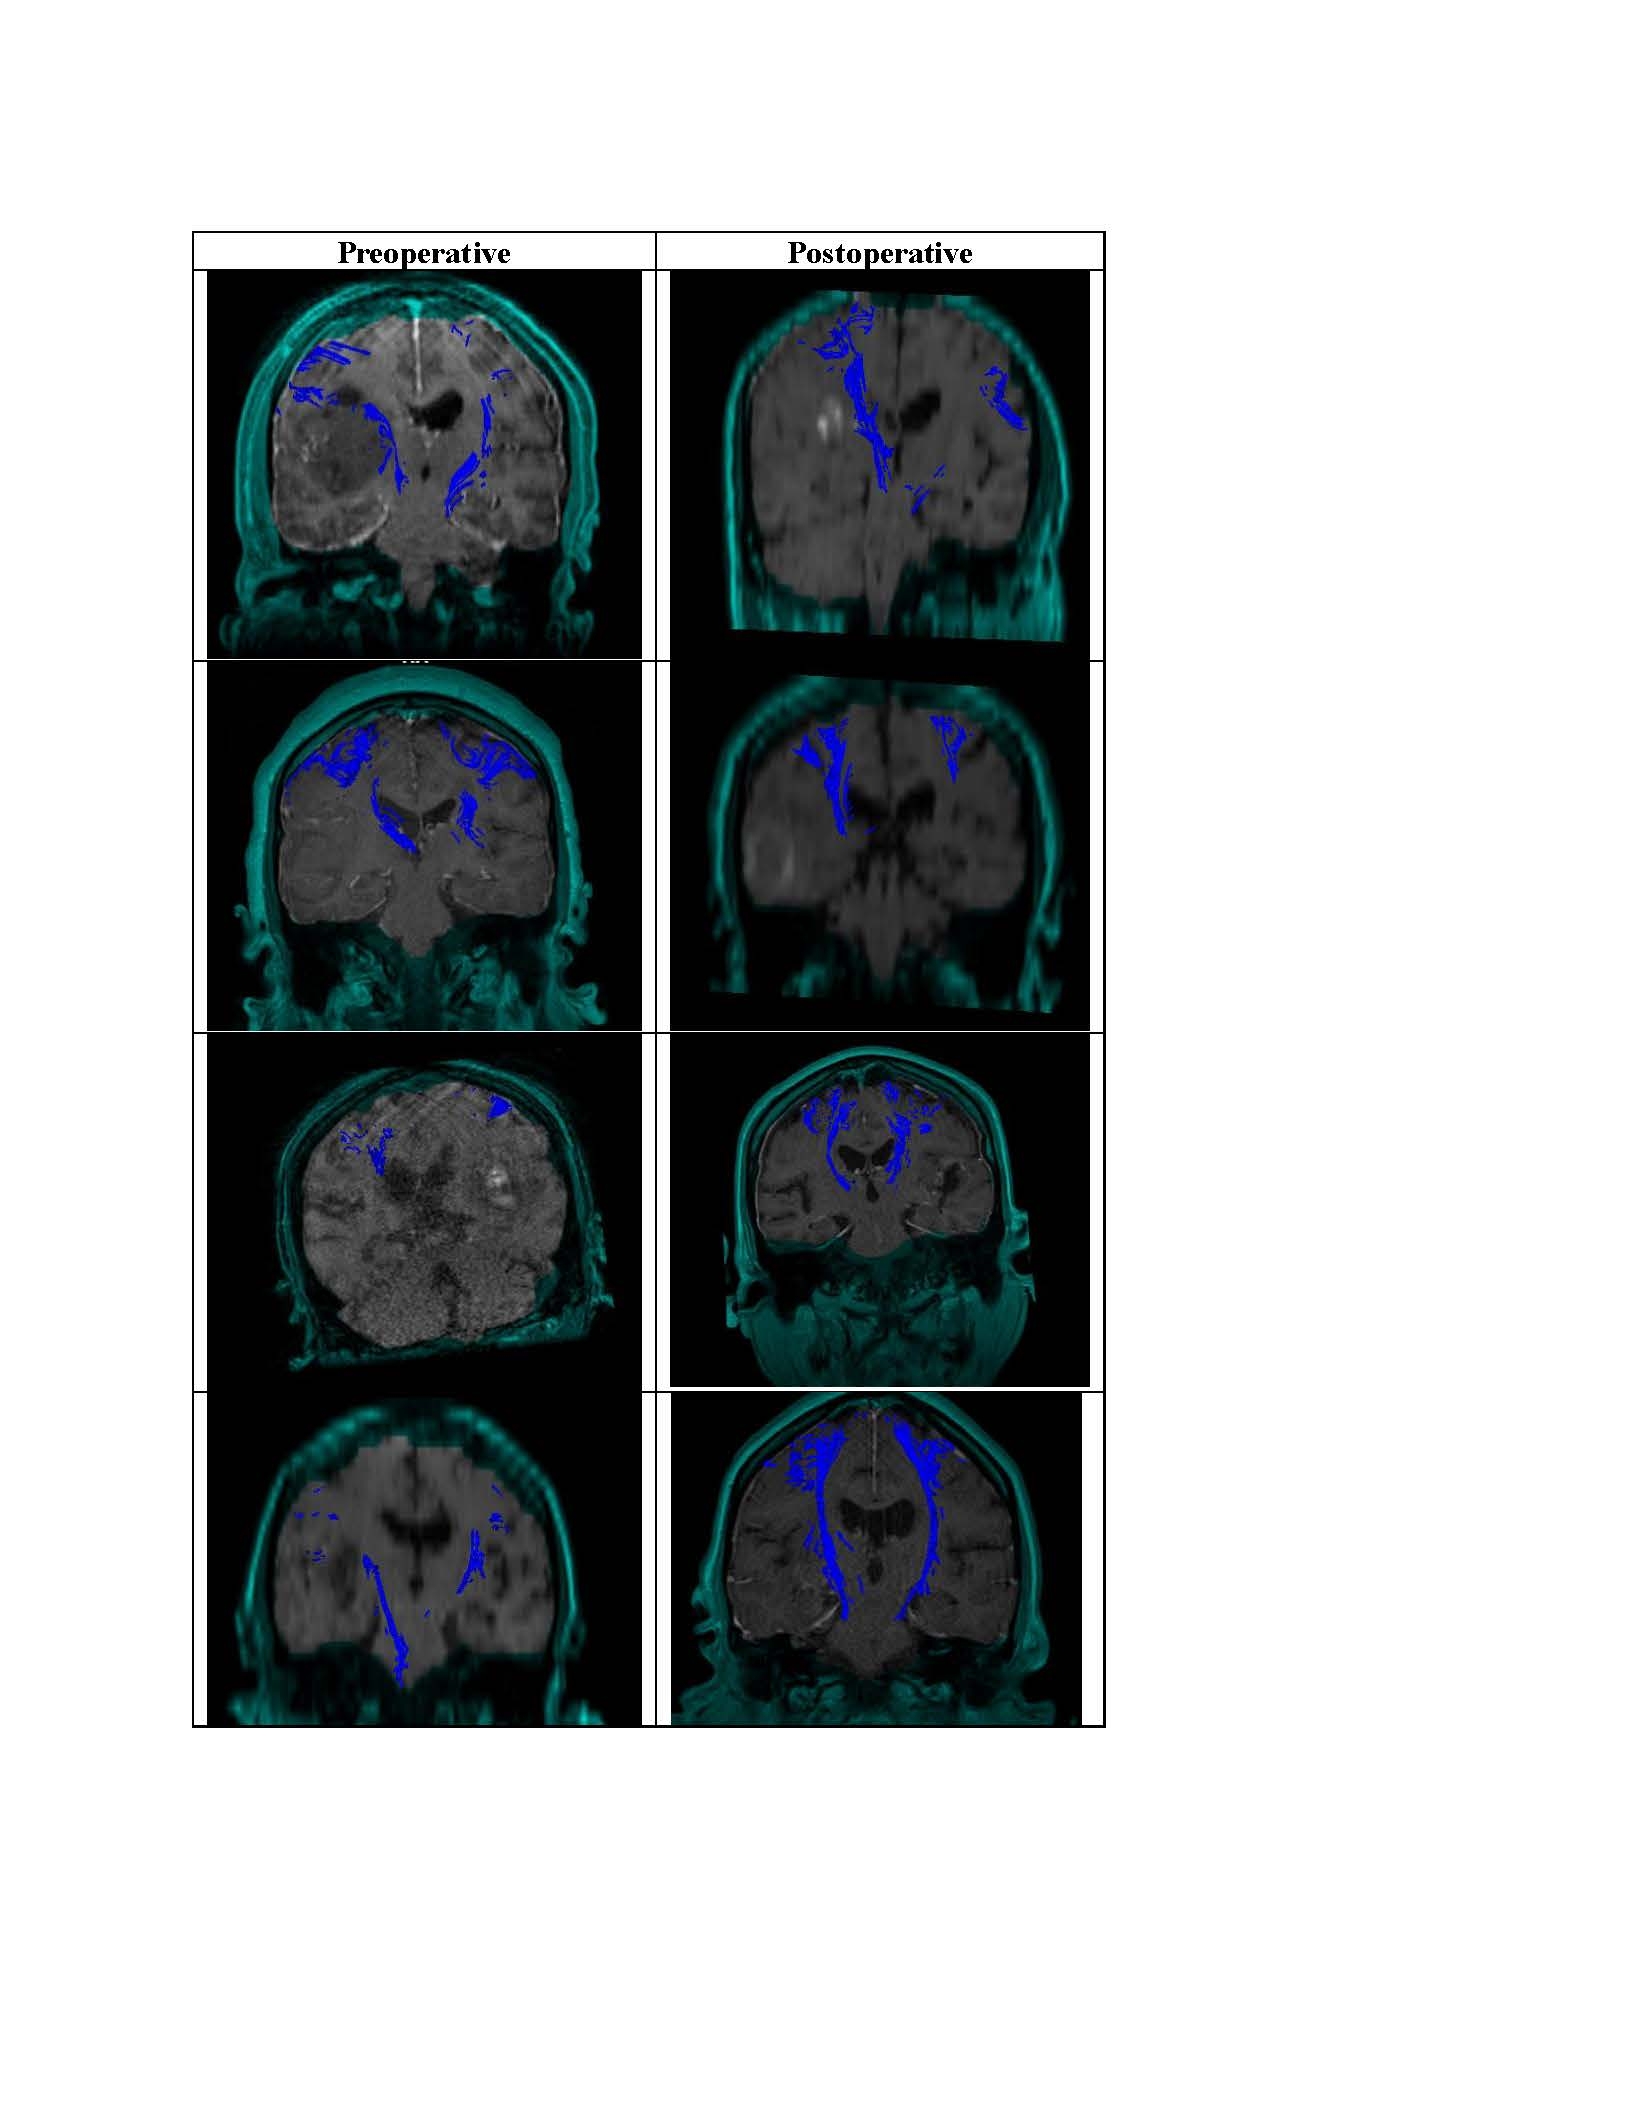

Eighteen patients with available peri-operative DTI data were included, 12 each with preoperative and postoperative DTI, seven with matched pre- and postoperative DTI. Preoperative geodesic anisotropy was significantly associated with both preoperative motor function on the contralateral hemibody (R=0.616, p=0.032, Pearson correlation) and at postoperative day one (R=0.606, p=0.038). Restoration of a deformed CST could be seen in several patients from preoperative to the immediate postoperative period (Figure 1). However, no preoperative or postoperative CST-DTI metrics were associated with motor scores at a median follow-up of 6.3 months post-ICH (p>0.05 for all comparisons). There was a significant increase in motor scores on the affected hemibody from postoperative day one to last follow-up (3.8±3.5 vs 6.3±6.8; p = 0.038, Wilcox signed-rank test).

Preoperative CST-DTI metrics are associated with both preoperative and immediate postoperative motor function after minimally invasive ICH evacuation. A restored CST after ICH evacuation could be seen in a subset of patients. However, neither preoperative nor immediate postoperative CST-DTI metrics were associated with longer-term motor function. Tractography from the perioperative period should be used with caution in providing motor prognosis.